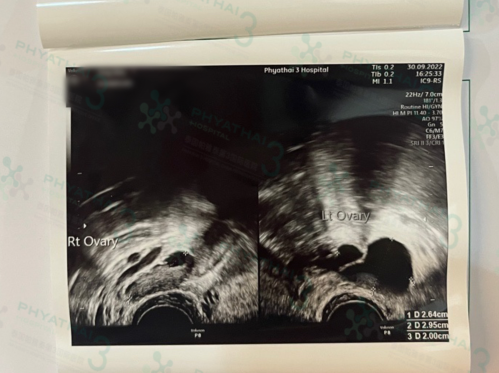

3、女性子宫问题

子宫是胚胎生长发育的重要场所,如果子宫出现异常,比如子宫内膜过厚、过薄,或是患有子宫疾病、畸形等问题,都会影响胚胎顺利着床及生长发育,甚至导致胚胎死亡,造成胎停、流产。